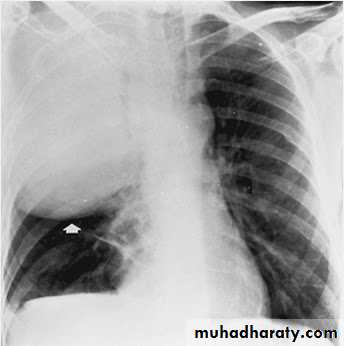

Lung abscess is a circumscribed collection of pus within the lung, is are potentially life threatening. They are often complicated to manage and difficult to treat

Lung abscesses are divided according to their duration into acute (< 6 weeks) and chronic (> 6 weeks) .

A primary abscess is one which develops as a result of primary infection of the lung. They most commonly arise from aspiration, necrotising pneumonia or chronic pneumonia, e.g. pulmonary tuberculosis

Some organisms are particularly prone to causes significant necrotising pneumonia resulting in cavitation and abscess formation. These include :

Staphylococcus aureus

Klebsiella sp: Klebsiella pneumonia

Pseudomonas sp

Plain film

The classical appearance of a pulmonary abscess is a cavity containing an air-fluid level. In general abscesses are round in shape, and appear similar in both frontal and lateral projections.

Lung abscess

Very important

Empyema vs pulmonary abscess1.relationship to adjacent bronchi / vessels

abscesses will abruptly interrupt bronchovascular structures

empyema will usually distort and compress adjacent lung

2.split pleura sign thickening and separation of visceral and parietal pleura is a sign of empyema

3.abscesses have thick irregular walls

empyema are usually smoother

4.angle with pleura

abscesses usually have an acute angle (claw sign)

empyema have obtuse angles